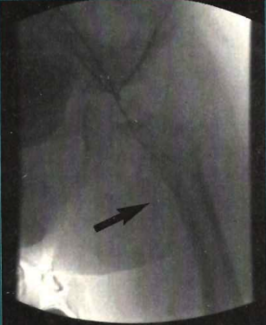

A 60-year-old man with a history of cardiac arrest 16 years prior presented via ambulance with substernal pressure of 2 hour duration. An electrocardiogram revealed prominent ST-segment elevation in the inferolateral and apical leads.